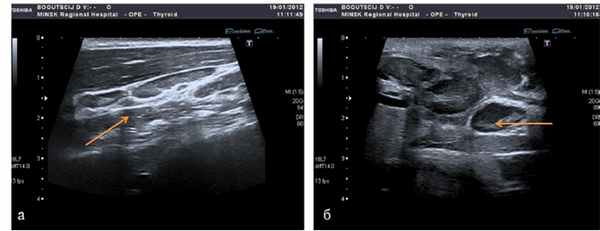

Полипозиционное рентгенологическое исследование шеи и грудной клетки с контрастированием пищевода при подозрении его перфорации выполнено в 100% наблюдений. УЗИ шеи на аппарате экспертного класса в серой шкале (В-режим) было показано для уточнения диагноза у 32,1% пациентов проспективной группы. Это позволило дифференцировать стадии воспалительной инфильтрации (рисунок 1), фазу абсцедирования, пути распространения гнойных затеков. У 5 (9,4%) пациентов применили пункцию предполагаемых гнойных очагов на шее под УЗ-контролем с целью диагностики и возможного дренирования. Компьютерная томография для уточнения диагноза медиастинита понадобилась 13,2% пациентов. Видеоэзофагогастродуоденоскопия для подтверждения перфорации пищевода понадобилась 32 из 63 пациентов (50,8%). При подозрении пищеводно-бронхиального свища в 2 наблюдениях (6,1%) выполнено комбинированное видеоэндоскопическое исследование: эзофаго- и бронхоскопия. Обоснована и внедрена с 2003 г. видеоторакомедиастиноскопия и -томия (4 наблюдения).

а - межфасциальная флегмона, б - распространение флегмоны на глубокие клетчаточные пространства (указаны стрелкой)

Рисунок 1 - УЗИ мягких тканей шеи